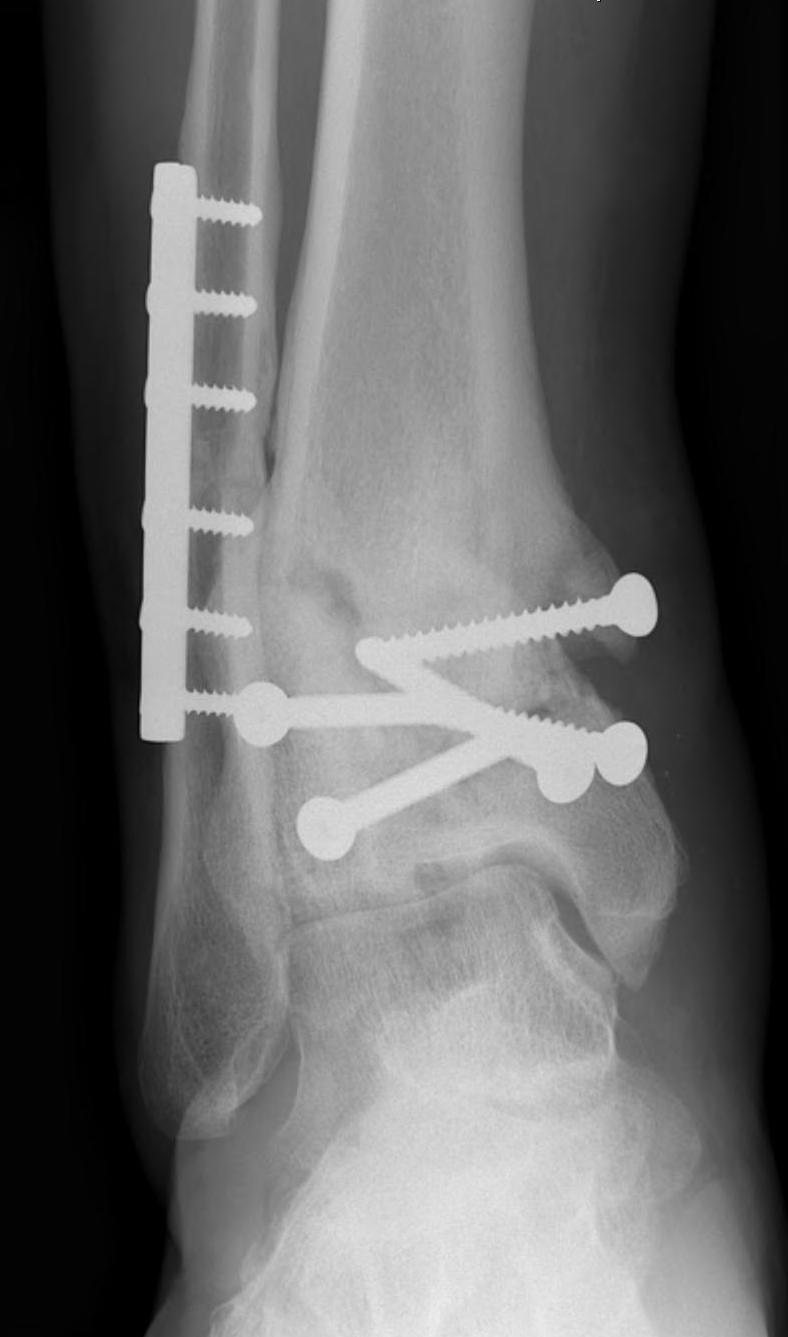

Tibial Plafond Pre External Fixator APTibial Plafond Pre External Fixator LateralTibial Plafond Post External Fixator APTibial Plafond Post External Fixator Lateral

Tibial Plafond CT AxialTibial Plafond CT SagittalPlafondTibial Plafond ORIF APTibial Plafond ORIF Lateral